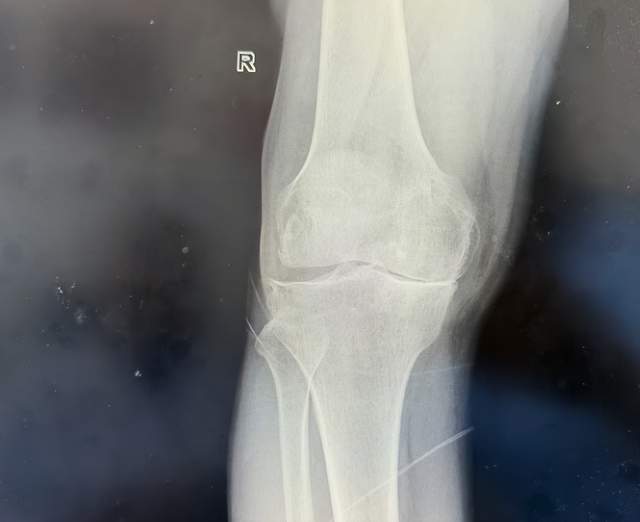

张大叔的右膝MR显示:半月板撕裂、软骨III级损伤、骨髓水肿……“就像轮胎磨穿了还漏气,膝盖里没有一块好地方。”尹绍猛解释道。传统方案需切除更多骨质,而生物型置换通过精准截骨,最大限度保留健康骨量。

术前影像